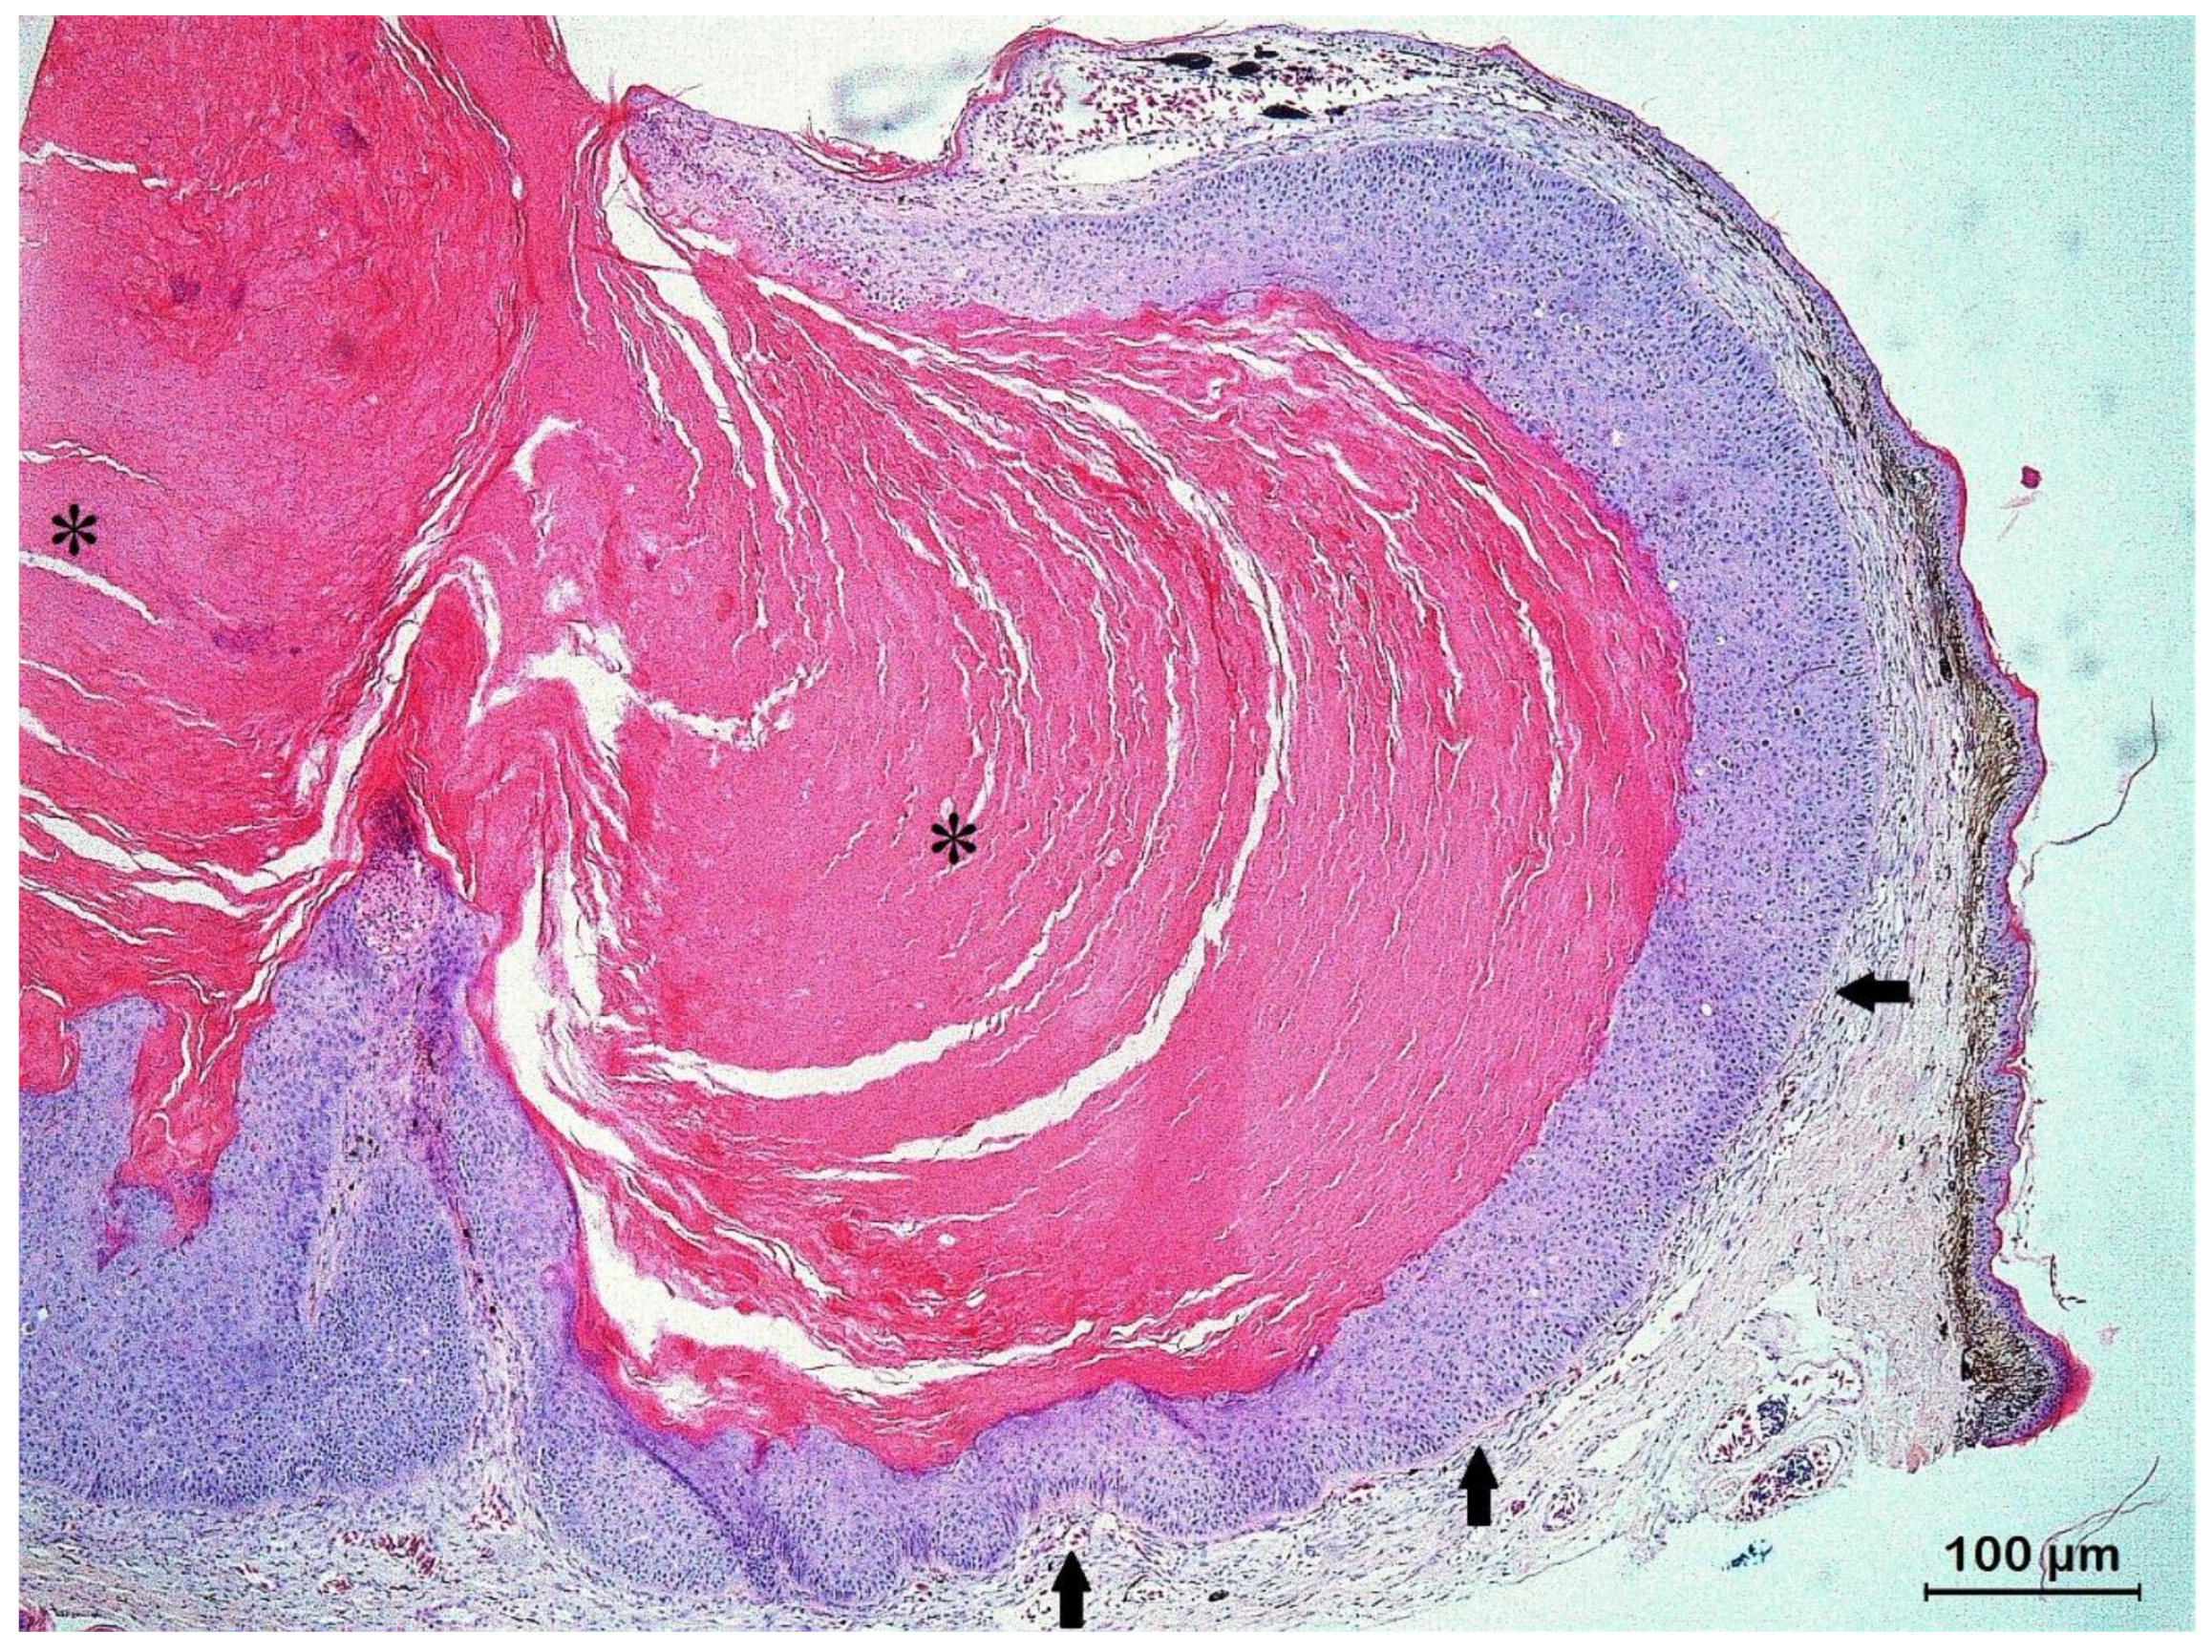

3.2. Histopathology and IHC